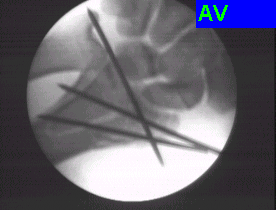

Case:4 Comminuted Intra – Articular Lower End Fracture Radius

A patient, aged 46 years following vehicular accident came with swollen painful wrist & hand. He had been diagnosed to have closed comminuted fracture lower end of right Radius. He was treated operatively with closed reduction & ‘K’ wiring under regional Anaesthesia.

Pre-Op

Pre-op Lateral

Post-op AP

One and Half Months Follow-Up